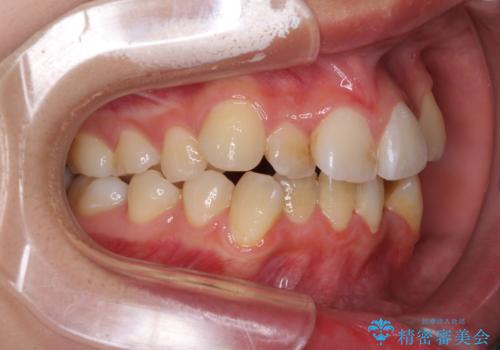

- 上下前歯のデコボコと、それによる磨きづらさを気にして来院された患者様です。

叢生解消のため、上下左右第一小臼歯4本を抜歯し、ワイヤー装置にて矯正治療を行うこととしました。